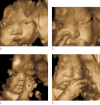

Diagnostic ultrasound (DUS) is, arguably, the most common technique used in obstetrical practice. From A mode, first described by Ian Donald for gynecology in the late 1950s, to B mode in the 1970s, real-time and gray-scale in the early 1980s, Doppler a little later, sophisticated color Doppler in the 1990s and three dimensional/four-dimensional ultrasound in the 2000s, DUS has not ceased to be closely associated with the practice of obstetrics. The latest innovation is the use of artificial intelligence which will, undoubtedly, take an increasing role in all aspects of our lives, including medicine and, specifically, obstetric ultrasound. In addition, in the future, new visualization methods may be developed, training methods expanded, and workflow and ergonomics improved.